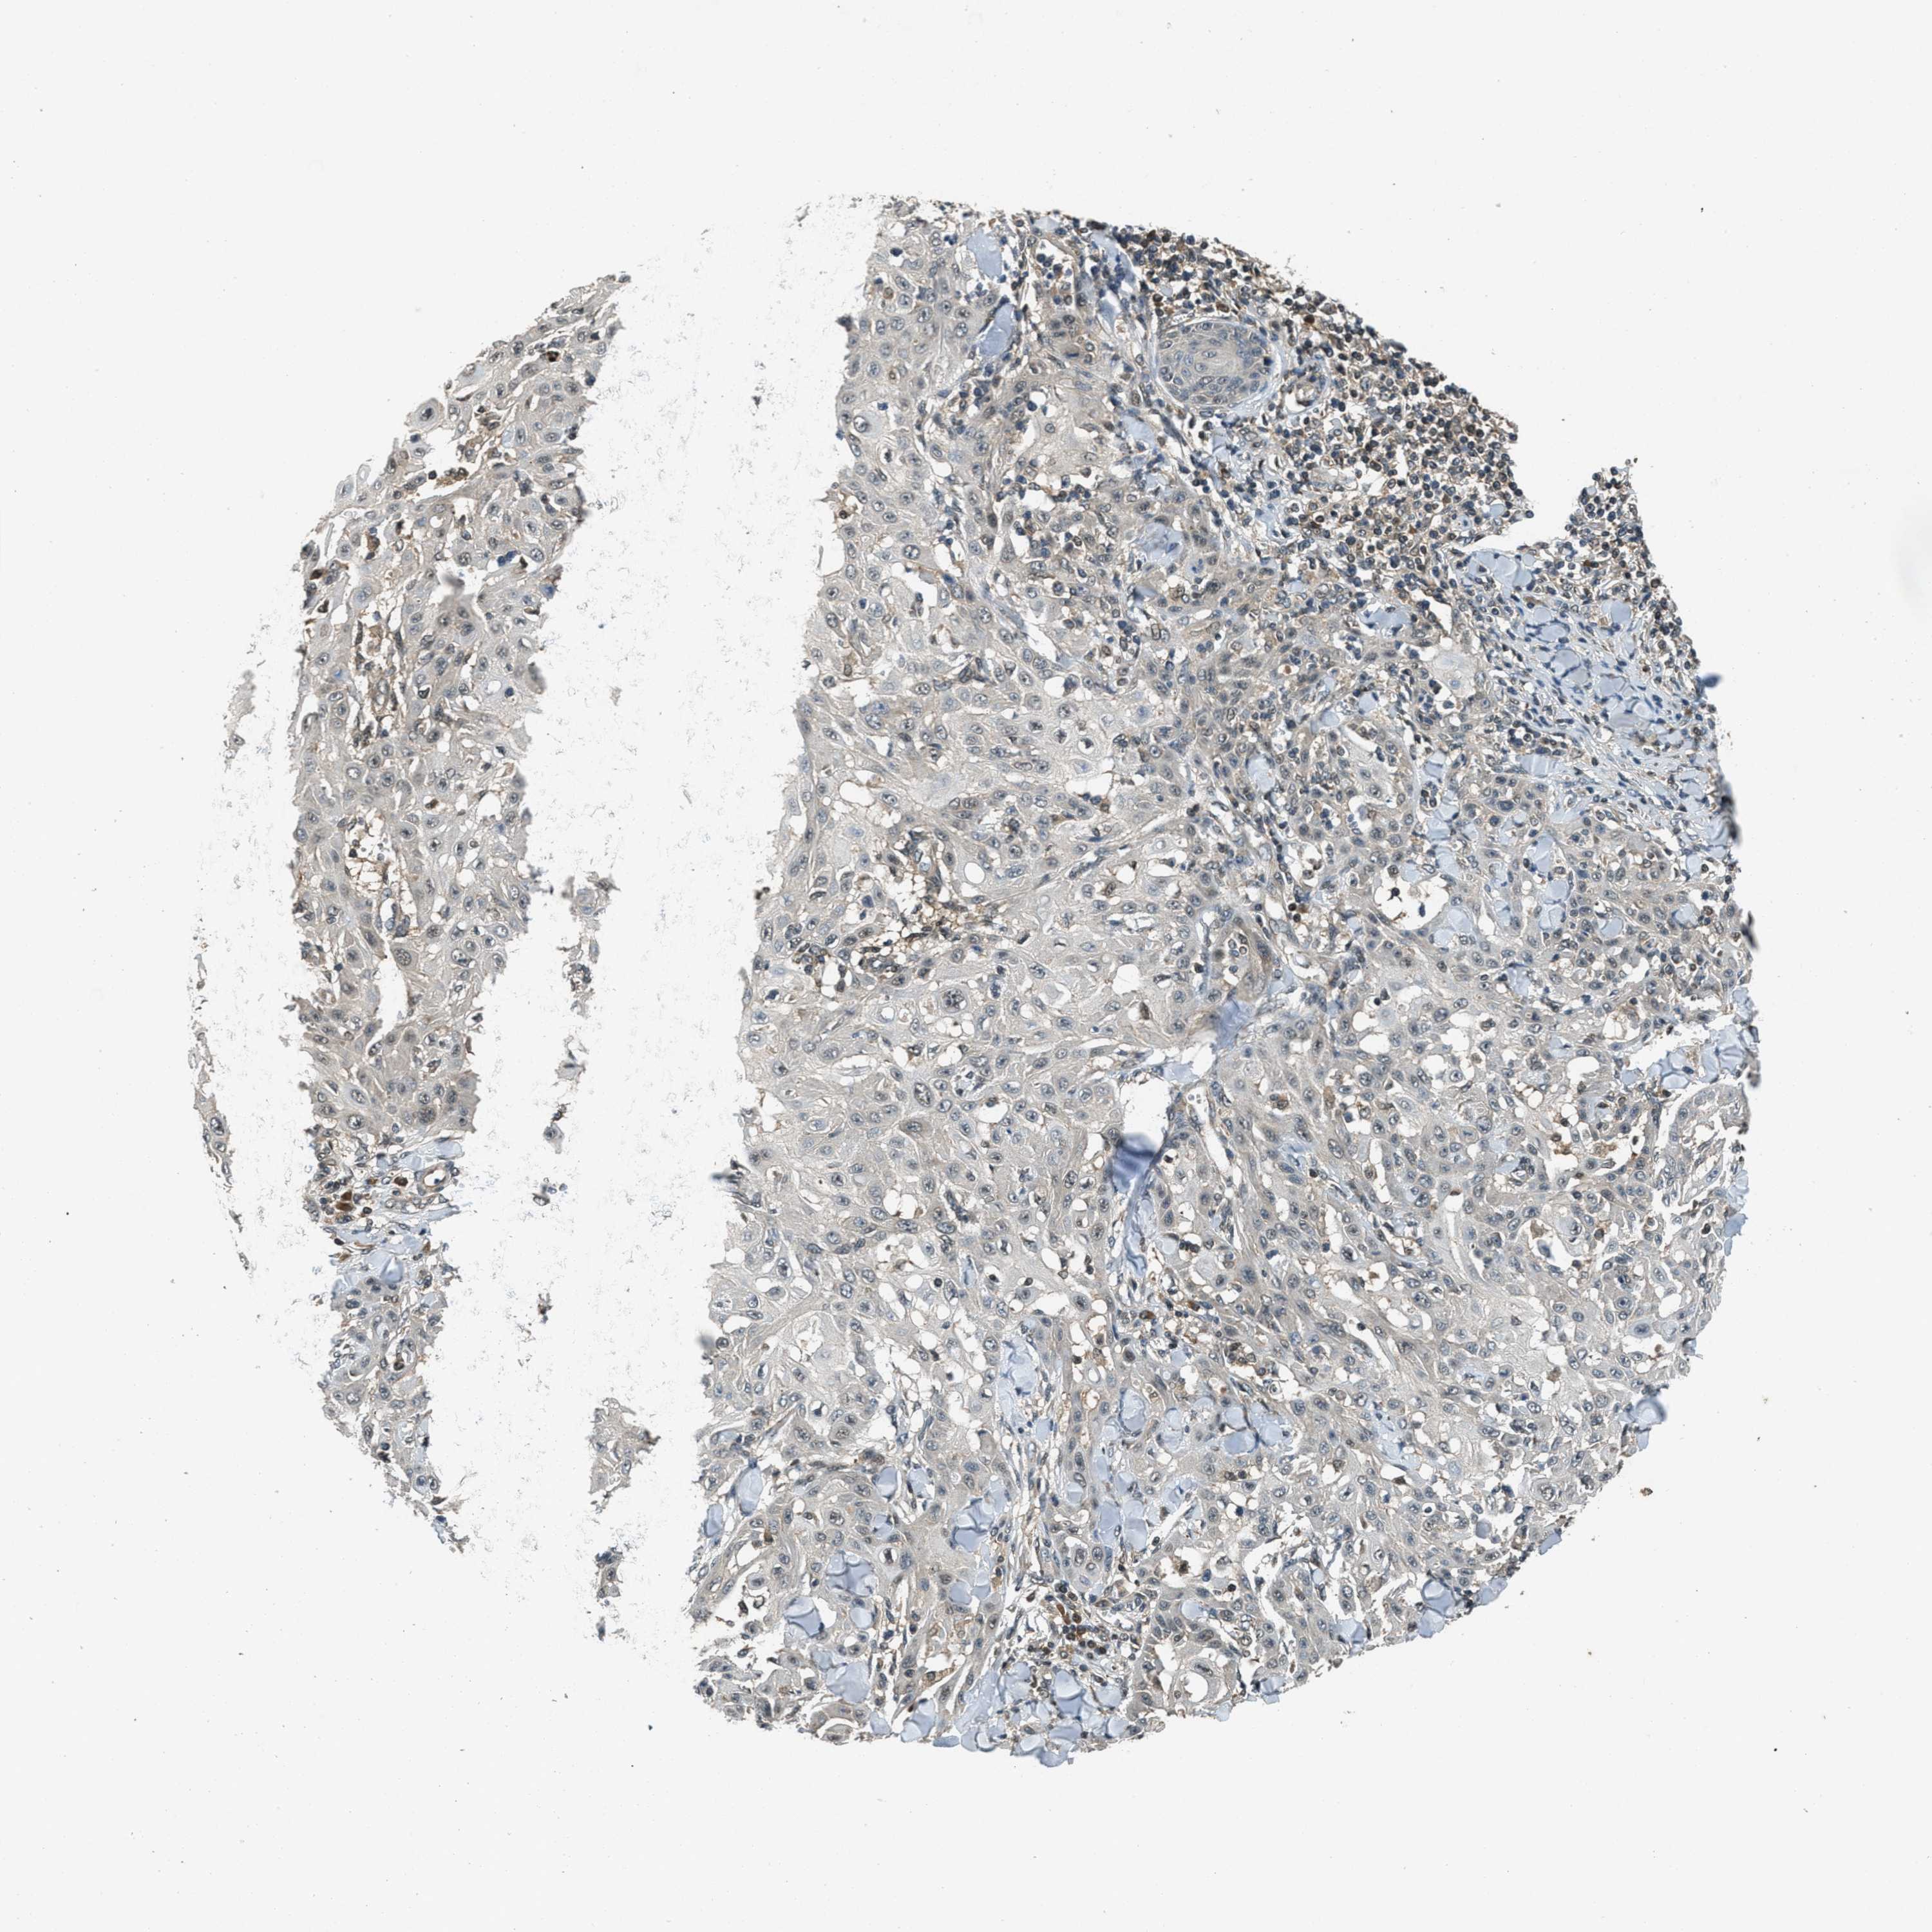

SKIN CANCER - Protein expressioni

A mouse-over function shows sample information and annotation data. Click on an image to view it in a full screen mode. Samples can be filtered based on level of antibody staining by selecting one or several of the following categories: high, medium, low and not detected. The assay and annotation is described here.

Each image is clickable and will lead to virtual microscopy that enables deeper exploration of all samples and also displays staining intensity scores, fraction scores and subcellular localization as well as patient and tissue information for each sample.

Antibody CAB017566

Staining

Medium

Intensity

Moderate

Quantity

75%-25%

Location

Cytoplasmic/membranous

Squamous cell carcinoma, NOS